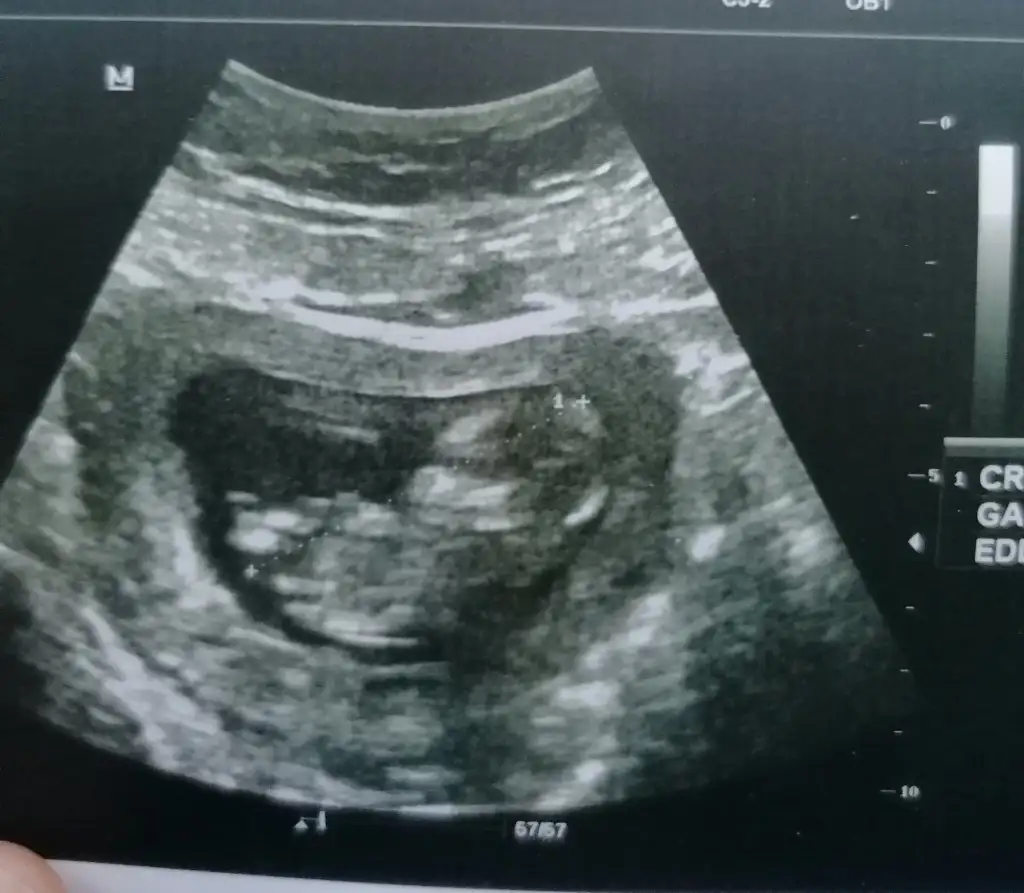

Sağlıkla gelsin yakışıklıMerhaba kızlar dr. Çıktık çok şükür herşey yolunda Allahım sağlıkla kucağımıza almayı nasip etsin bize. Veee cinsiyetimiz belli olduErkek geliyor

Sağlıkla gelsin inşallahMerhaba kızlar dr. Çıktık çok şükür herşey yolunda Allahım sağlıkla kucağımıza almayı nasip etsin bize. Veee cinsiyetimiz belli olduErkek geliyor

Ayyy maşallah canım sağlıkla kucağına alMerhaba kızlar dr. Çıktık çok şükür herşey yolunda Allahım sağlıkla kucağımıza almayı nasip etsin bize. Veee cinsiyetimiz belli olduErkek geliyor

Evet 12+4 olarak ileriden gidiyor biraz sağlıklı olsunda hayırlısı olsun inşallah.Sağlıkla gelsin yakışıklı